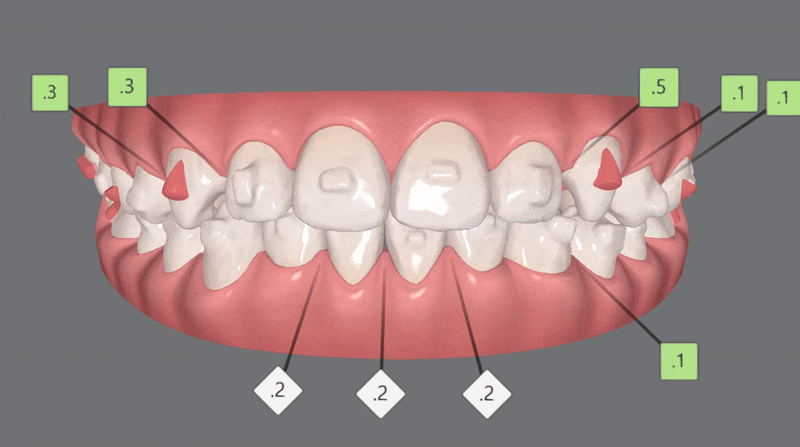

인비절라인퍼스트로 1차, 2차교정까지 마무리된 사진입니다 :)

치열이 고르지 않고

반대교합으로 아래턱이 도드라져 보였던 이전과 달리

청소년기인비절라인 교정 후

반대교합이 개선되고

맹출되지 않았던 앞니의 공간이 생기며

치아들이 제 위치를 찾고

정중선이 맞아지고 치열이 가지런해지면서

보다 자연스러운 미소를 지어주었습니다 :)